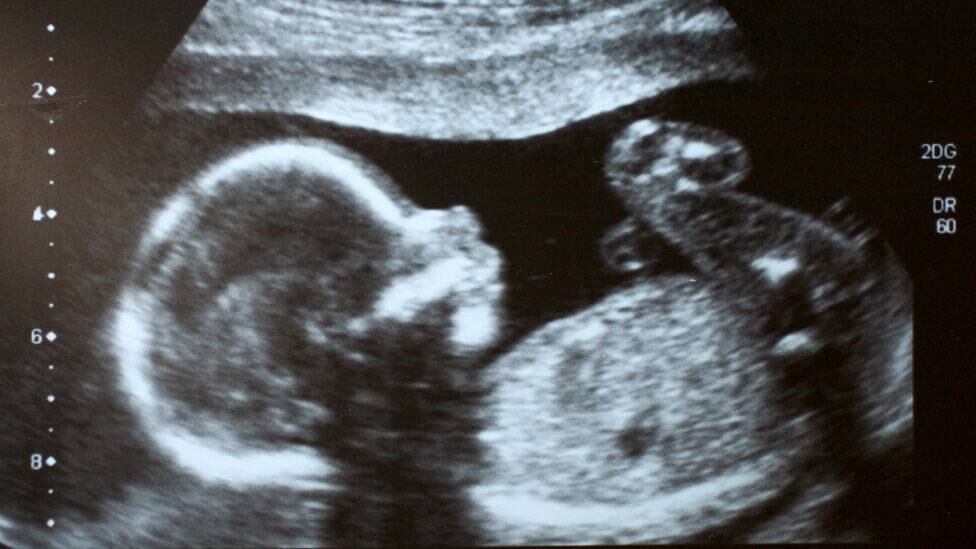

Pero no fue un nacimiento como cualquier otro: el varón, llamado Michael, pudo llegar al mundo sin problemas gracias a que, cuando estaba en la panza de su mamá, fue operado para corregirle un problema que podría haber sido fatal.

Así, el pequeño se convirtió en el primer caso de cirugía fetal exitosa de la historia.

El médico que lo operó, Michael Harrison, desarrolló la técnica de la cirugía intrauterina trabajando en el Hospital de Niños de la Universidad de California en San Francisco (UCSF).